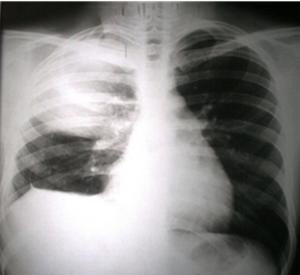

Volver a los detalles del artículo Absceso hepático amebiano con empiema pleural derecho. A propósito de un caso